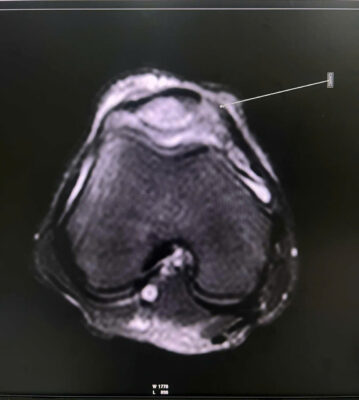

1. MỞ ĐẦU 📚Tổn thương phối hợp giữa dị vật nội khớp háng và mạc giữ bánh chè – đùi trong (Medial Patellofemoral Ligament – MPFL) là tình huống hiếm gặp trong chấn thương chỉnh hình. 👉Các biểu hiện lâm sàng thường không đặc hiệu, dễ bị che lấp bởi triệu chứng đau đa vùng sau chấn thương, dẫn đến nguy cơ bỏ sót tổn thương nội khớp nếu không được đánh giá hình ảnh đầy đủ. 💥Việc phối hợp giữa khám lâm sàng tỉ mỉ và chẩn đoán hình ảnh chuyên sâu (CT, MRI) đóng vai trò quyết định trong việc phát hiện sớm, định hướng điều trị và tiên lượng phục hồi chức năng vận động cho người bệnh. 2. CA LÂM SÀNG 📚 Bệnh nhân nam, sau chấn thương biểu hiện đau vùng háng và gối phải, hạn chế vận động chi dưới cùng bên, đã khám ở BV tuyến trước không xác định được tổn thương. Đêm ngày 03/10, chuyển đến Bệnh viện Quân y 17, qua khám lâm sàng ghi nhận đau sâu vùng háng, đau mặt trong gối khi vận động gấp duỗi, khi sờ ấn, không có biến dạng. 📚Hình ảnh CT scan khớp háng phát hiện một dị vật nhỏ nằm trong ổ khớp háng phải, nghi là mảnh xương vỡ gây kẹt khớp sau chấn thương. MRI khớp gối phải cho thấy tổn thương mạc giữ bánh chè – đùi trong (MPFL) tại chỗ bám vào xương bánh chè, kèm tràn dịch khớp nhẹ. 👉 Nhờ phối hợp chặt chẽ giữa bác sĩ lâm sàng và bác sĩ chẩn đoán hình ảnh, tổn thương phối hợp hiếm gặp này được xác định chính xác, giúp tránh bỏ sót dị vật nội khớp và mô mềm quanh gối khó phát hiện nếu chỉ dựa vào thăm khám. 👉Bệnh nhân được dự kiến lấy dị vật nội khớp háng bằng kỹ thuật ít xâm lấn, nội soi kết hợp màn hình tăng sáng hỗ trợ, bảo tồn mạc giữ khớp bánh chè – đùi trong do không gây di lệch xương bánh chè. 3. BÀN LUẬN 👉 Dị vật nội khớp háng là tổn thương ít gặp, thường thứ phát sau chấn thương gãy xương vùng chậu – ổ cối. Trong khi đó, rách MPFL là tổn thương hay gặp nhất trong trật khớp, gãy xương bánh chè cấp, nhưng hiếm khi xuất hiện đồng thời với dị vật nội khớp háng. Khi hai tổn thương này cùng tồn tại, triệu chứng thường chồng lấp, dễ dẫn đến chẩn đoán không đầy đủ hoặc điều trị chưa triệt để.

✓ Theo Guerrero và cộng sự, MRI là phương tiện hiệu quả nhất để nhận diện tổn thương MPFL và phân loại mức độ rách (tại điểm bám vào bánh chè, tại xương đùi hoặc rách đoạn giữa), trong khi CT giúp phát hiện chính xác các mảnh xương tự do hoặc dị vật trong khớp [3]. ✓ Các tác giả Selmene MA (2022) và Davis ES (2019) cũng khẳng định rằng kỹ thuật lấy dị vật nội khớp háng ít xâm lấn hoặc có hỗ trợ C-arm giúp giảm sang chấn mô mềm và rút ngắn thời gian hồi phục [1],[2]. ✓ Trong báo cáo này, việc phối hợp CT – MRI đã cho phép phát hiện đầy đủ cả hai tổn thương, đồng thời định hướng phẫu thuật hợp lý: lấy dị vật nội khớp nội soi, đồng thời khâu phục hồi cấu trúc mạc giữ khớp bánh chè – đùi trong nếu cần thiết. ✓ Cách tiếp cận này giúp hạn chế nguy cơ bỏ sót tổn thương nhỏ, bảo tồn cấu trúc khớp và phục hồi sớm chức năng vận động. 4. KẾT LUẬN ✓Tổn thương phối hợp giữa dị vật nội khớp háng và rách mạc giữ bánh chè – đùi trong là hiếm gặp và có thể bị bỏ sót nếu không được đánh giá toàn diện. ✓Sự phối hợp chặt chẽ giữa bác sĩ lâm sàng và chẩn đoán hình ảnh là yếu tố then chốt giúp chẩn đoán chính xác, lựa chọn chiến lược điều trị hợp lý, mang lại kết quả phục hồi tối ưu cho người bệnh. 📚Trường hợp tại Bệnh viện Quân y 17 là minh chứng cho năng lực chuyên sâu của đơn vị trong chẩn đoán và xử trí các tổn thương chấn thương chỉnh hình phức tạp, góp phần nâng cao chất lượng điều trị và an toàn người bệnh. 5. TÀI LIỆU THAM KHẢO [1]. Selmene MA, et al. Minimally invasive removal of intra-articular hip fragments. [Journal of Orthopaedic Case Reports]. 2022. [2]. Davis ES, et al. A novel technique to remove posterior intra-articular hip foreign bodies via anterior approach. Tech Orthop. 2019;34(4):302-306. [3]. Guerrero P, Li X, Patel K, Brown M, Busconi BD. Medial patellofemoral ligament injury patterns and associated pathology in lateral patella dislocation: an MRI study. Sports Med Arthrosc Rehabil Ther Technol. 2009;1:17. [4]. Conlan T, Garth WP Jr, Lemons JE. Evaluation of the medial soft tissue restraints of the extensor mechanism of the knee. J Bone Joint Surg Am. 1993;75:682-693. [5]. Nomura E, Inoue M, Osada N. Anatomical analysis of the medial patellofemoral ligament of the knee, especially the femoral attachment. Knee Surg Sports Traumatol Arthrosc. 2005;13:510-515. [6]. Smith A, et al. Medial patellofemoral ligament reconstruction: a systematic review. Orthop J Sports Med. 2024;12(1):1-10.